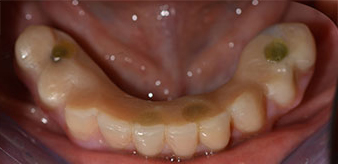

The 64-year-old patient presented with residual dentition of teeth 38, 33 and 43 and a clasp denture in the mandible (Fig. 1 and 2).

Following an explanation of the various treatment options open to her, the patient decided on extraction of the residual dentition in the mandible, an immediate implantation and treatment with the Fast & Fixed method (bredent medical), whereby the provisional fixed denture is screwed onto four implants on the same day as the surgery. The goal was to operate on the patient on the Friday so that she could assist in the oral examinations on the following Monday.

A three-dimensional cone beam computed tomography scan (CBCT, Planmeca) was performed to aid planning and minimize risks. This revealed that the quality and quantity of the available bone were sufficient for the surgery and immediate restoration using the Fast & Fixed method. Following the protocol for this concept, the implants are inserted at 35, 32, 42 and 45. Angling the distal implants by up to 45° shifts the emergence profile to posterior and generates a larger support polygon (Fig. 3).